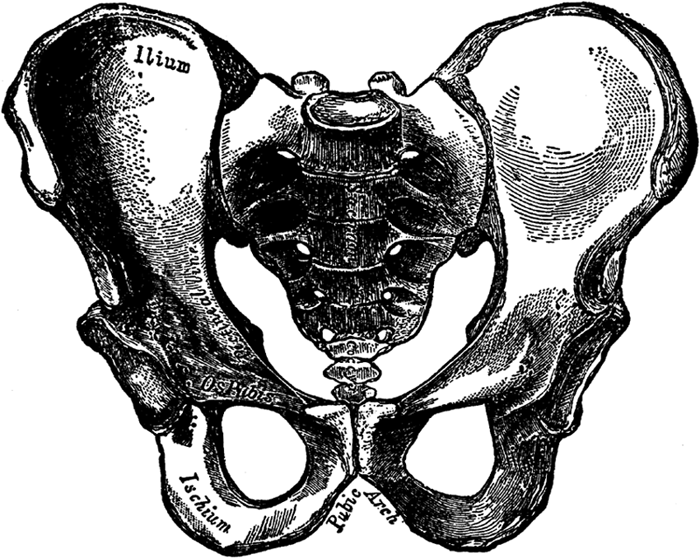

The Pelvis of the Male.

The internal sex organs are situated in the lower part of the abdominal cavity, the part that is called the pelvis, or pelvic cavity. The meaning of the word pelvis in Latin is basin. The pelvis, also referred to as the pelvic girdle or pelvic arch, forms a bony basin, and is composed of three powerful bones: the sacrum, consisting of five vertebræ fused together and constituting the solid part of the spine, or vertebral column, in the back, and the two hipbones, one on each side. The two hipbones meet in front, forming the pubic arch.

The hipbones are called in Latin the ossa innominata (nameless bones) and each hipbone is composed of three bones: the ilium, the ischium, and the os pubis. The thighs are attached to the hipbones, and to the hipbones are also attached the large gluteal muscles, which form the buttocks, or the "seat."

The pelvis of the female differs considerably from the pelvis of the male. The female pelvis is shallower and wider, less massive, the margins of the bones are more widely separated, thus giving greater prominence to the hips; the sacrum is shorter and less curved, and the pubic arch is wider and more [48]rounded. All this is necessary in order to permit the child's head to pass through. If the female pelvis were exactly like the male pelvis, a full-term living child could never pass through it. The two illustrations show the differences between the male and female pelvis very clearly.

Note particularly the differences in the pubic arches: in the male pelvis it is really more of an angle than an arch. Also note how much longer and more solid the sacrum (with its attached bone, called the coccyx[2]) is in the male pelvis. The differences in the pelves (the plural of pelvis is pelves) of the male and female become fully marked at puberty, but they are present as early as the fourth month of intra-uterine life.